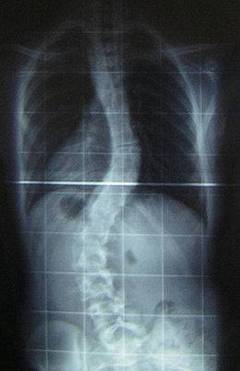

La scoliosi è una curvatura della colonna vertebrale caratterizzata per eccedere più di 10° con rispetto al piano frontale del corpo. Le cause possono essere molte, se non esiste un’origine strutturale si può trattare con esercizi muscolari.